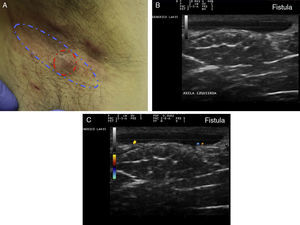

Criterios ecográficos de las lesiones elementales de la hidradenitis supurativaLos principales hallazgos ecográficos de la HS incluyen una alteración difusa del patrón dérmico, un engrosamiento dérmico, la presencia de pseudoquistes dérmicos, el engrosamiento del folículo piloso y la detección de colecciones fluidas y de tractos fistulosos (figs. 3–5)83.

A continuación se produciría una alteración del patrón dérmico, inicialmente perifolicular y posteriormente difuso, con la presencia de un engrosamiento dérmico, que refleja el marcado proceso inflamatorio subyacente principalmente provocado por diferentes mediadores de la inmunidad innata. Así, la mayor o menor hipoecogenicidad y la extensión de la misma nos puede orientar hacia el grado de inflamación subyacente que presenta la enfermedad (figs. 3–5)83.

Finalmente se producirían los tractos fistulosos (estructuras hipoecoicas o anecoicas en banda que atraviesan diferentes estructuras a través de las diferentes capas de la piel en la dermis o en la hipodermis, conectados a la base de estructuras foliculares alteradas [fig. 5 A-C]).